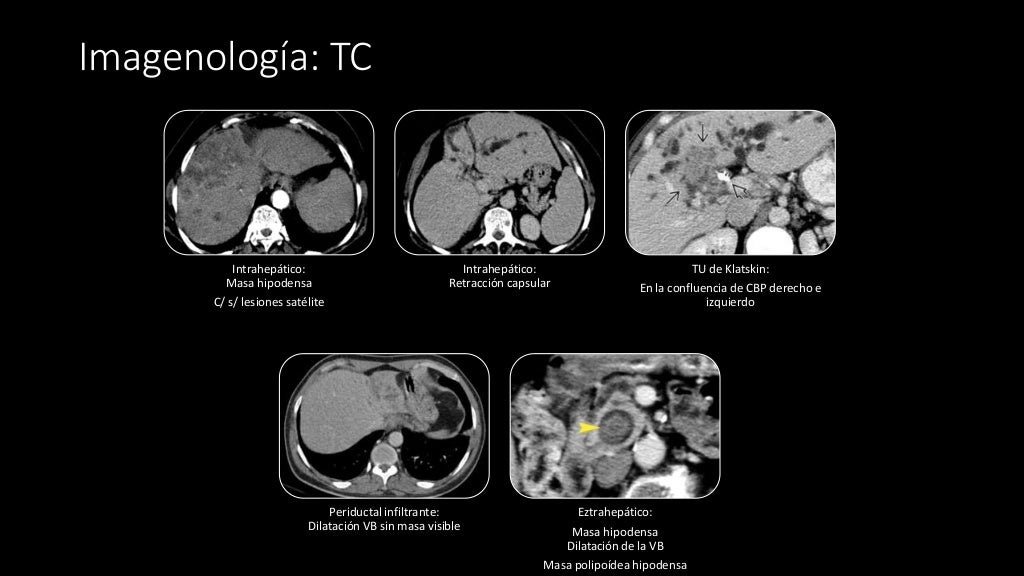

Colangiocarcinoma

Cholangiocarcinoma CT wikidoc

Stadiazione prechirurgica, in paziente con colangiocarcinoma

Manejo y diagnóstico del colangiocarcinoma formador de masa a propósito